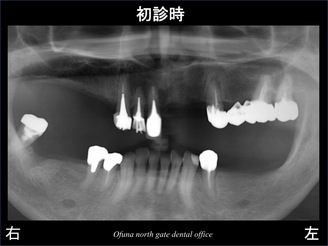

以下は初診のレントゲン写真です。

歯がない部分が多数あります。

現在は 義歯(入れ歯)を使用していますが、上顎の前歯などは義歯を外すと歯がない状態になるので審美的に問題があるので どうにかしたい とのご希望があり来院されました。

インプラント治療をご希望されて来院されましたが、

欠損が多数あるので、歯がない部分全てにインプラント治療を行うと治療費がかなりかかります。